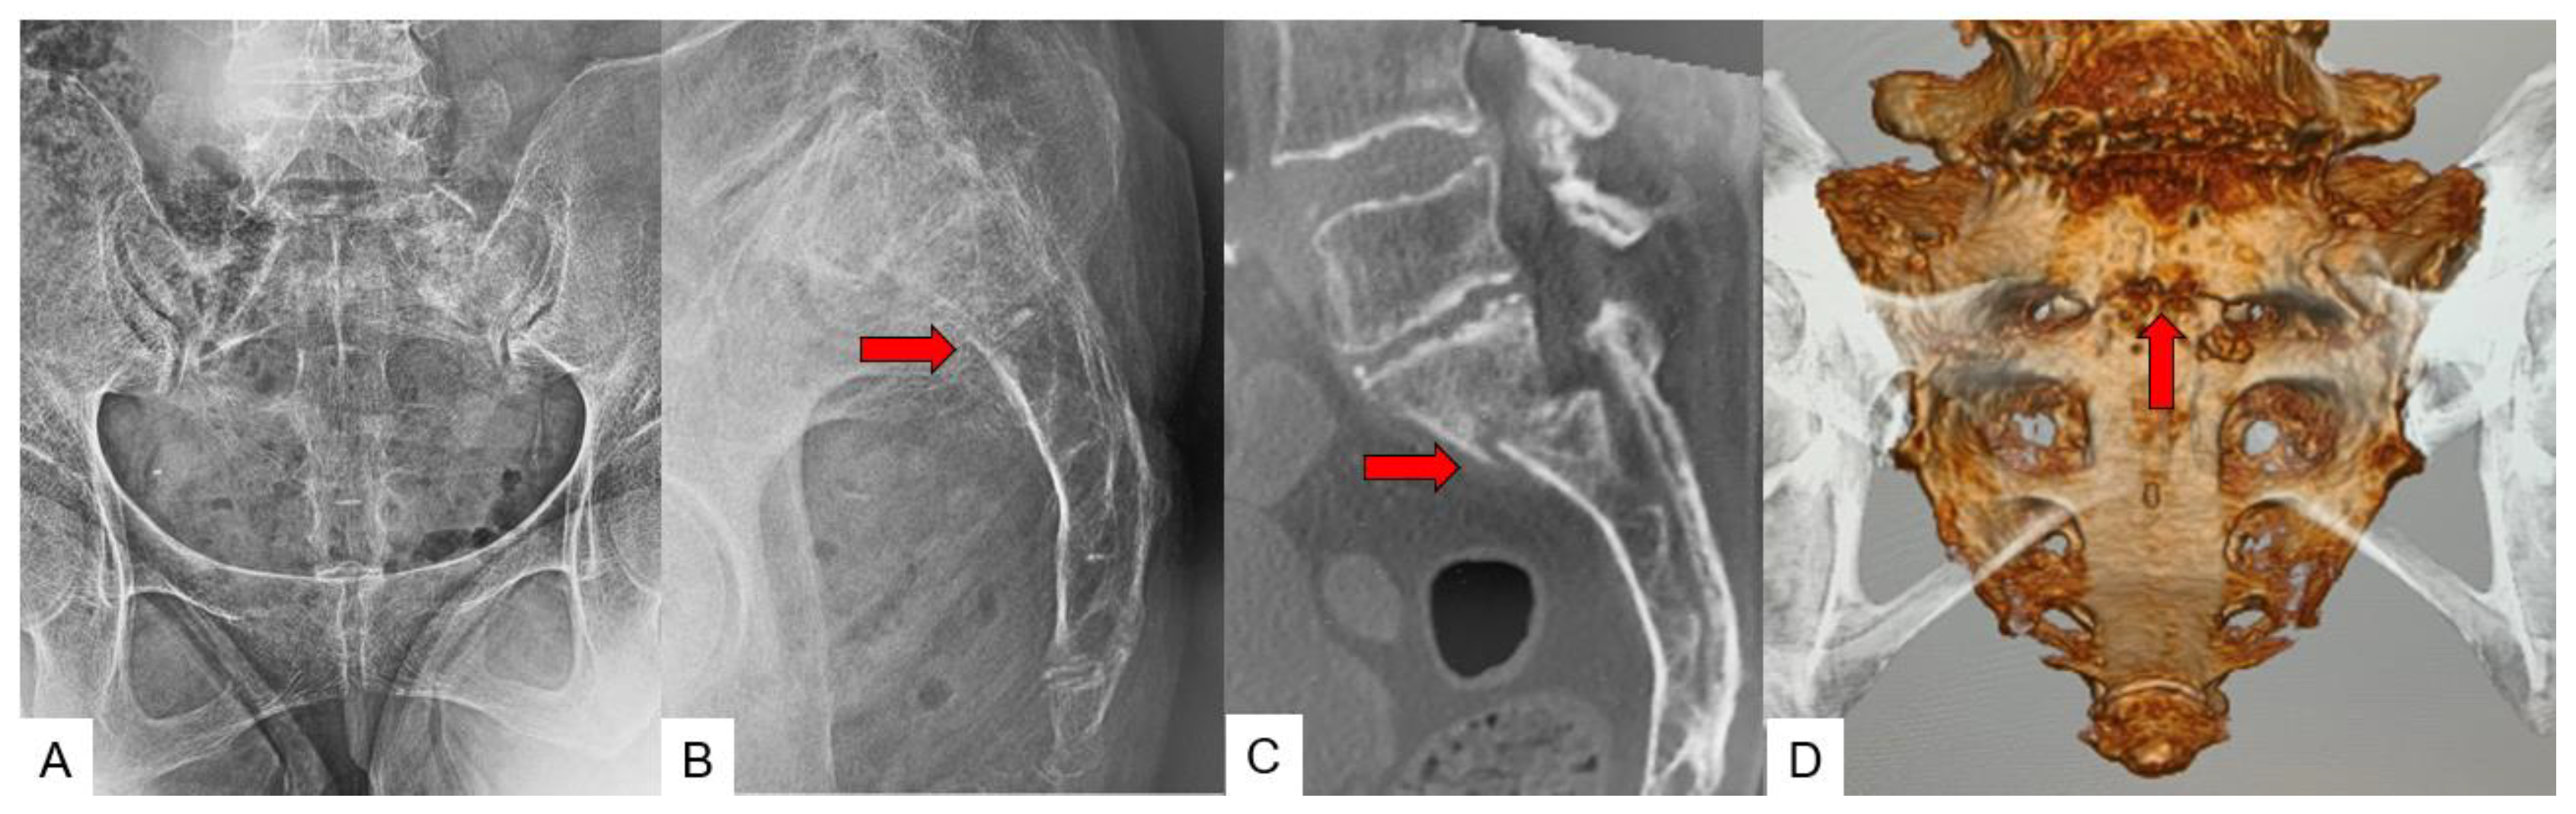

3.3. SIF Fracture Pattern

3.4. Typical SIF Case